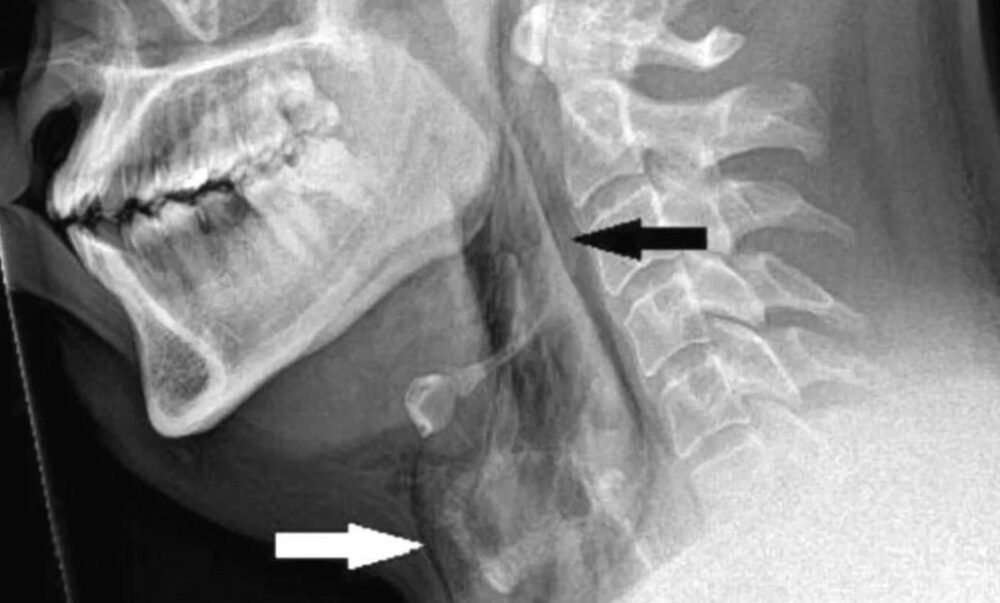

La historia, documentada este mes en la revista médica BMJ Case Reports, señala que el paciente, de unos 30 años, comenzó a sufrir un intenso dolor en el cuello inmediatamente después querer evitar un fuerte estornudo tapándose la nariz y manteniendo la boca cerrada al mismo tiempo, mientras conducía. Rápidamente acudió a urgencias del hospital Ninewells de la ciudad de Dundee, donde fue sometido a una radiografía y tomografía de cuello y tórax, que revelaron un pequeño “desgarro traqueal” a nivel de la tercera y cuarta vértebra torácica.

El hombre no requirió tratamiento quirúrgico y fue medicado con analgésicos y fármacos para la alergia debido a sus antecedentes de rinitis alérgica, cuyo síntoma típico suelen ser los estornudos. Cinco semanas después se realizó una tomografía computarizada que confirmó que tanto el desgarro como cualquier otra anomalía traqueal habían desaparecido.

Se sospecha que lo sucedido al paciente fue consecuencia de una “rápida acumulación de presión” en la tráquea provocada por la maniobra de bloquear las fosas nasales y la boca. La presión en las vías respiratorias superiores durante un estornudo es de 1 a 2 kilopascales (kPa), pero si la boca y la nariz están cerradas la esta puede aumentar hasta 20 veces, explican.

Los médicos que investigaron el incidente no se habían encontrado antes con un caso similar y explican que “una perforación traqueal espontánea es una afección rara y potencialmente mortal”. Por lo general, son causadas por lesiones traumáticas después de ciertos procedimientos médicos (tiroidectomía, intubación traumática, traqueotomía percutánea), por una lesión corrosiva esofágica o como resultado de traumatismos cortantes y contundentes, señalaron.